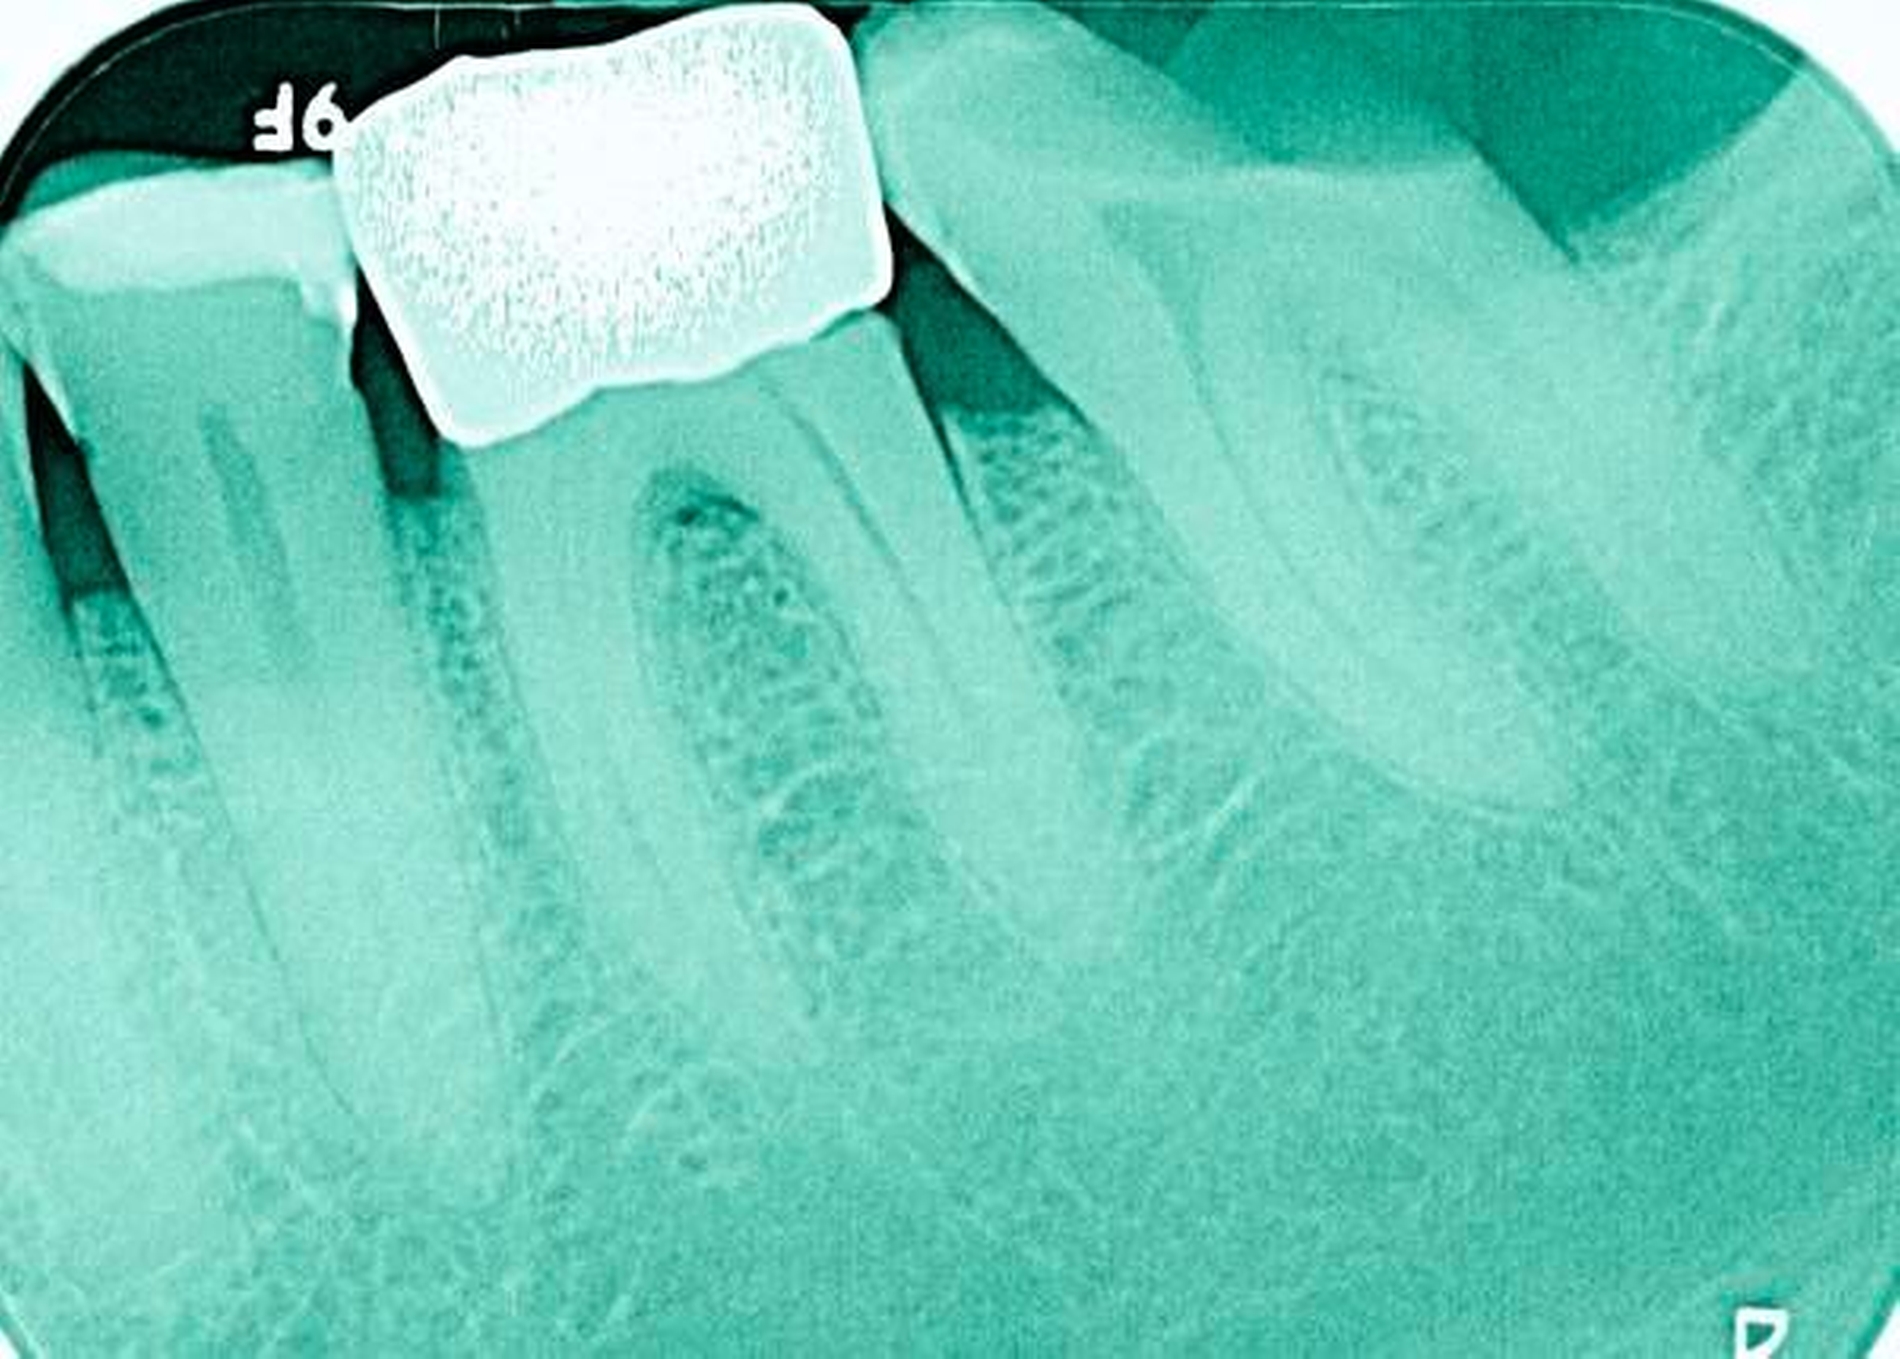

Abbildung 4: Anliegen eines 76,5-jährigen Patienten (Anfrage per E-Mail). Zitat: „Mich plagt eine … Entzündung des Mundraums, die auch das Zahnfleisch meiner Zahnstummel angreift, weshalb ich nur noch Breiartiges zu essen vermag. Ein Angsthase wie ich geht zum Zahnarzt NUR unter dem Eindruck akuter Schmerzen!“

Damit wird die Hygienefähigkeit zumindest partiell verbessert und Spielraum für künftige Planungen und Vorgehensweisen unter besseren Bedingungen belassen. Das Procedere ist in den Abbildungen 4 und 5 beschrieben. Bei dem in Abbildung 4 vorgestellten Patienten lag eine Oralphobie im Seniorenalter vor. Die Verlaufsbeschreibung macht deutlich, dass selbst im fortgeschrittenen Alter eine Adaptation an zahnärztliche Interventionen im Einzelfall noch möglich ist.

4. Vorgehen bei frakturierten Zahnkronen/Wurzelresten

Üblicherweise werden frakturierte Zahnkronen beziehungsweise Wurzelreste restaurativ wieder aufgebaut oder es erfolgt eine Extraktion. Im Seniorenalter erscheint es hingegen manchmal als Kompromissmaßnahme vertretbar, Wurzelreste vorerst zu belassen und etwa mit adhäsiv eingebrachtem Komposit knapp über Gingivahöhe abzudecken. Dies bietet sich vor allem dann an, wenn die Wurzelkanäle bereits obliteriert und endodontische Interventionen nicht erforderlich sind (Tabelle 4) [Staehle et al., 2017].